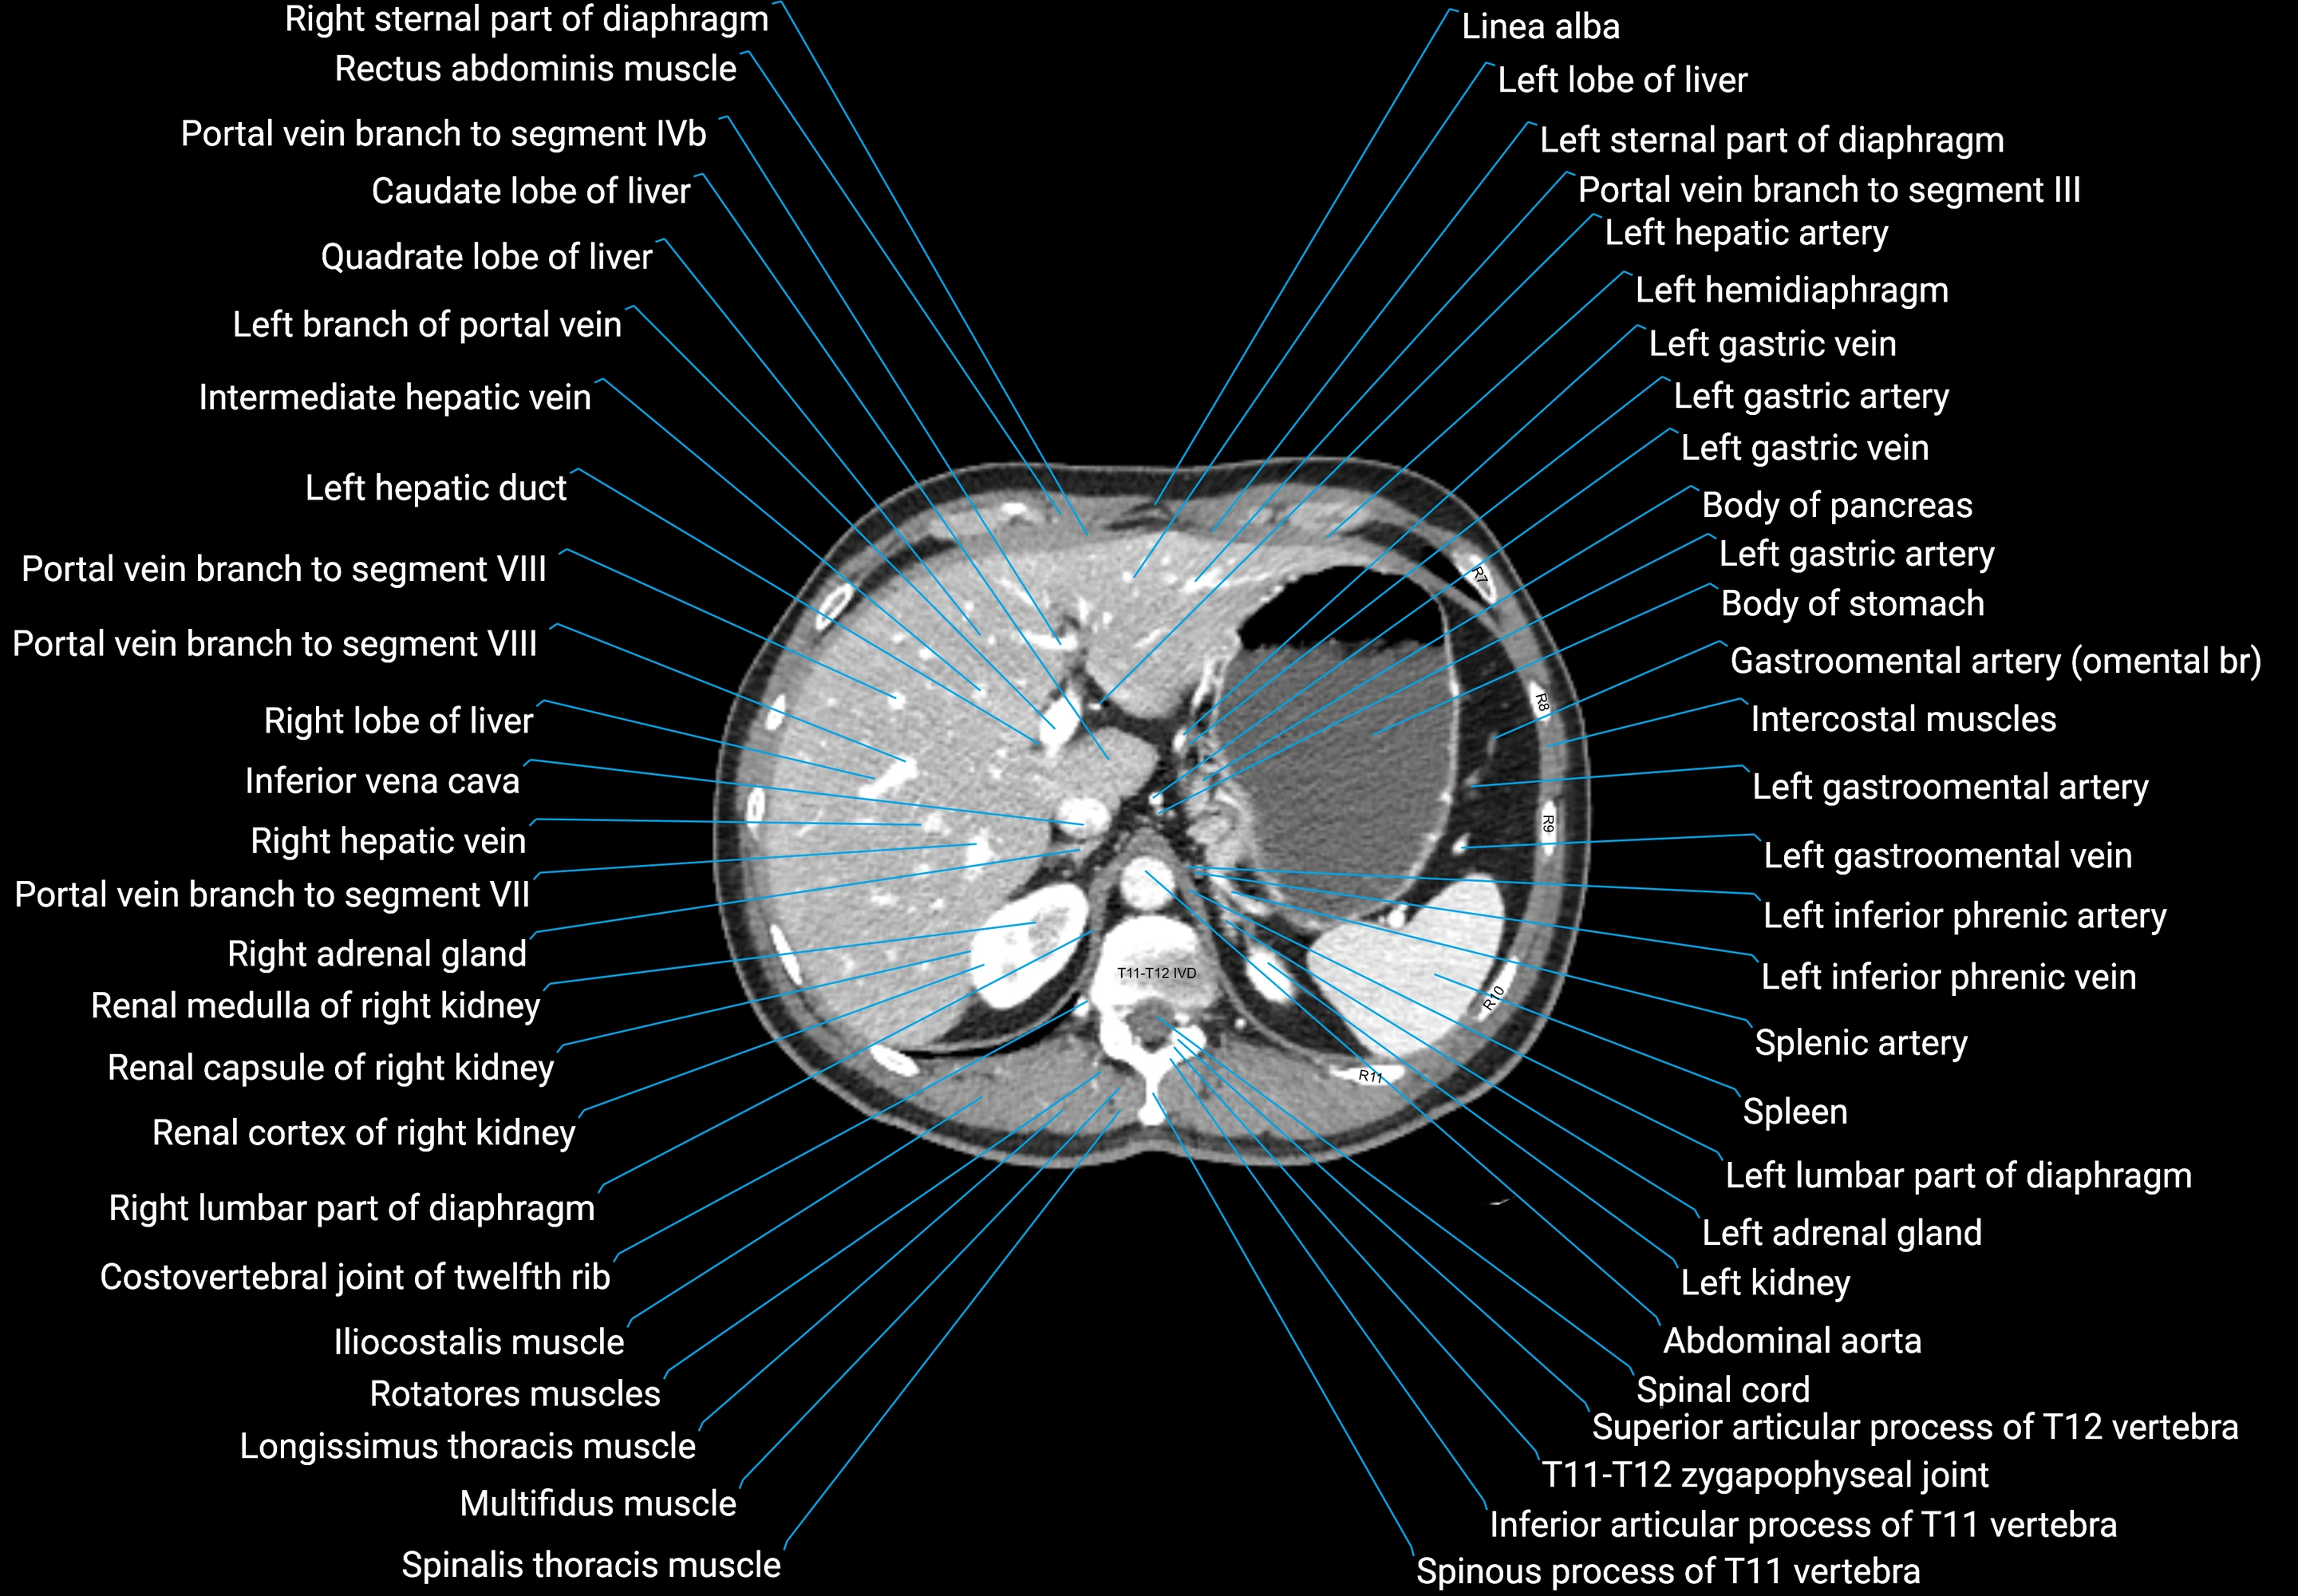

CT images